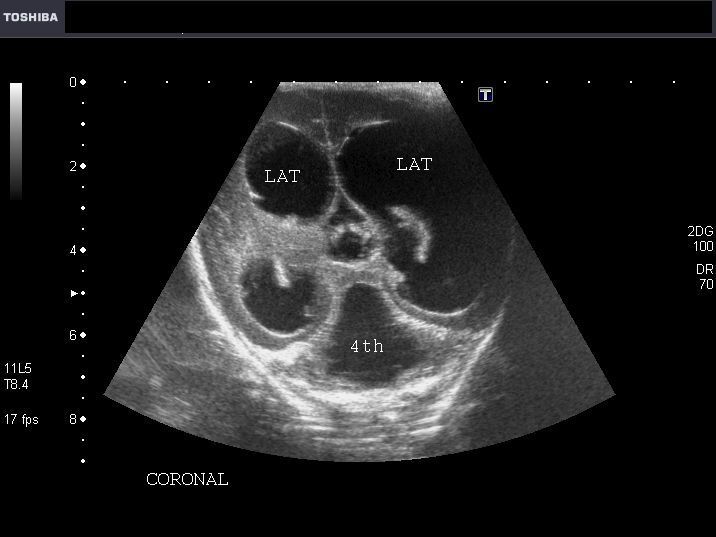

Another case of Hydrocephalus in neonate

Sonography of this neonatal brain shows severe dilatation of both lateral ventricles, the 3rd ventricle and also the fourth ventricle. The lateral ventricles measure 2.3 cms. at the atria. There is evidence of thinning of the cerebral tissue. The echogenic choroid plexus is seen within the lateral ventricles, near the thalami. There was no evidence of spinal dysraphism or extra- CNS anomalies. These ultrasound images are suggestive of communicating or extraventricular obstructive hydrocephalus. Here, the site of obstruction appears to be outside the ventricular system or failure of absorption of the CSF.